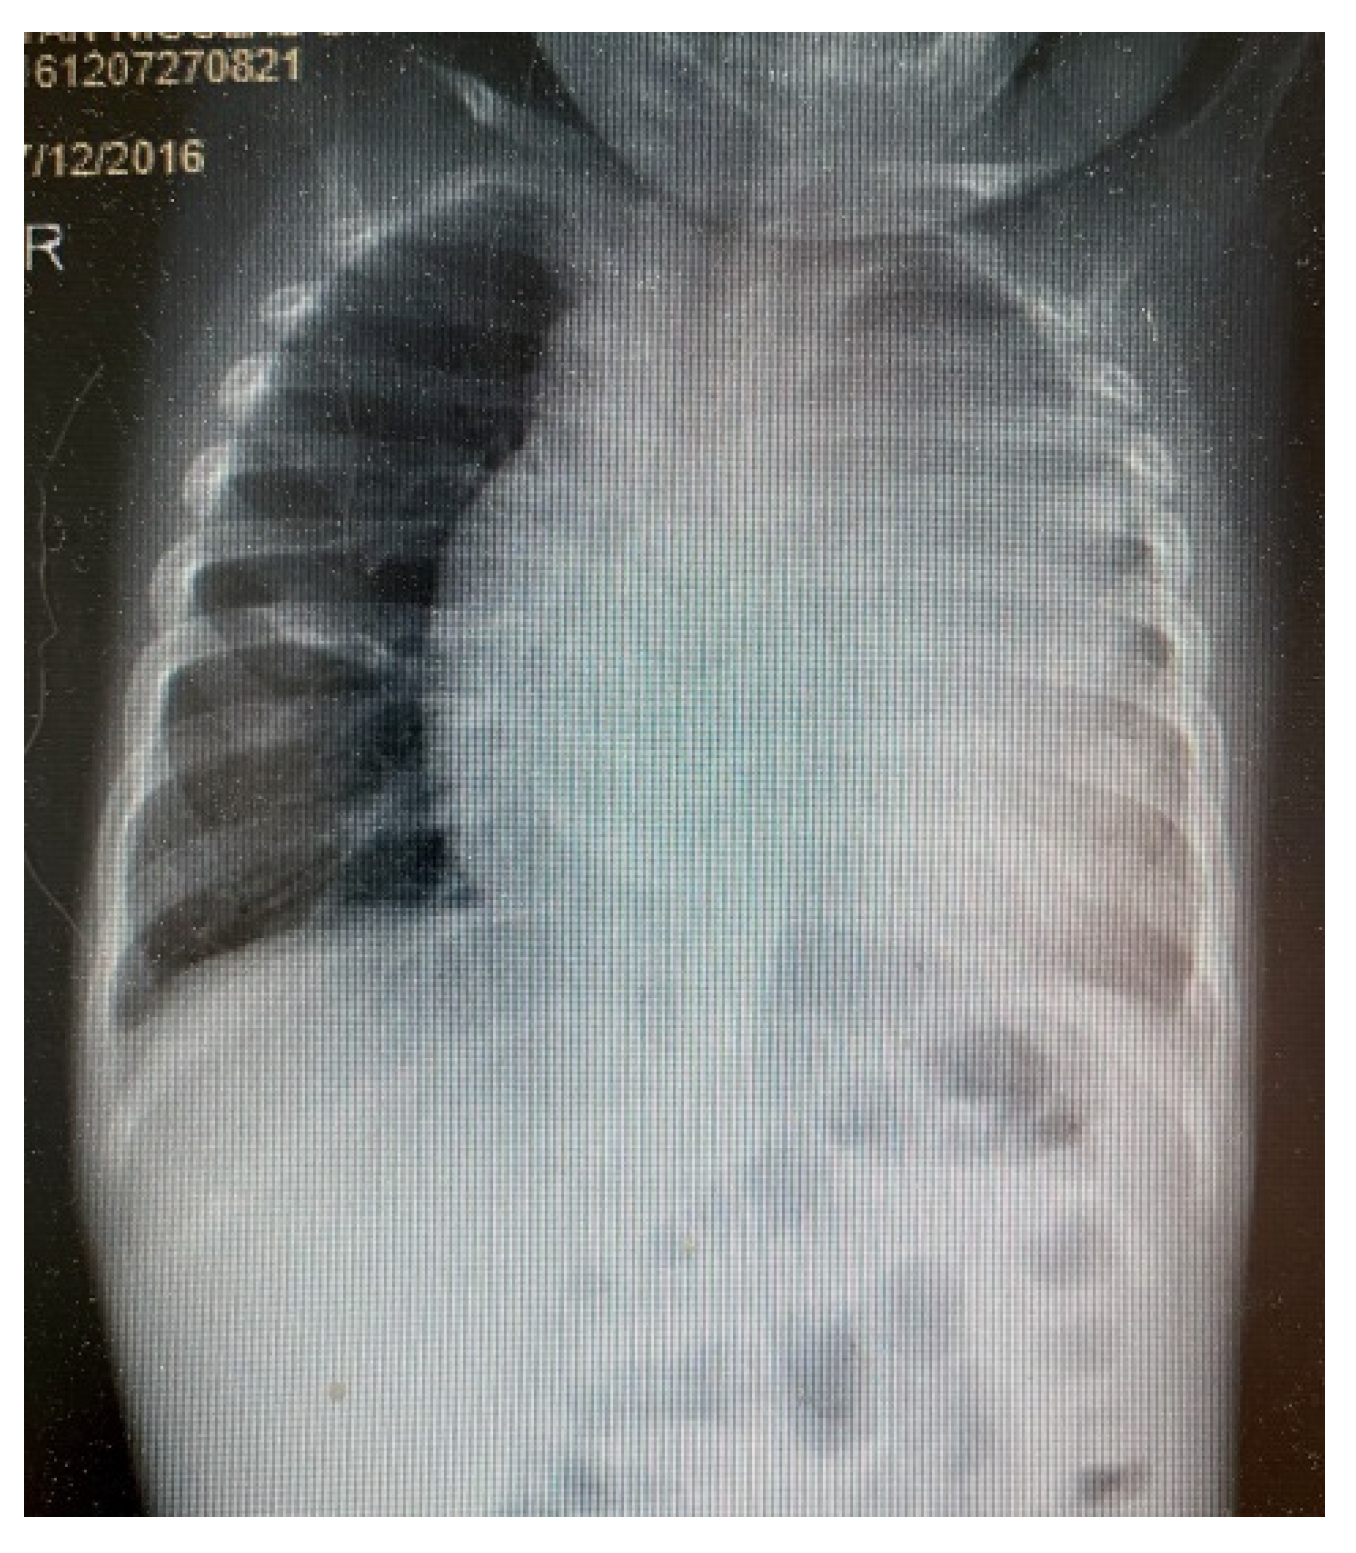

3. Results